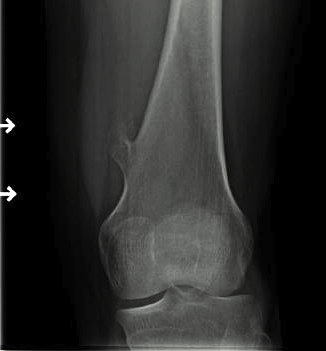

Suspicious features

- growth after maturity

- increased thickness of cartilage cap on CT / MRI - > 2 cm

- increasing pain

- increased calcification / bony erosion / lytic areas on xray

X-ray

Cortical and marrow continuity

1. Pedunculated - has a stalk, points away from joint

Pedunculated

Protuberant bony lesion arising adjacent to physis

- directed away from joint

- cortical bone and marrow space continuous